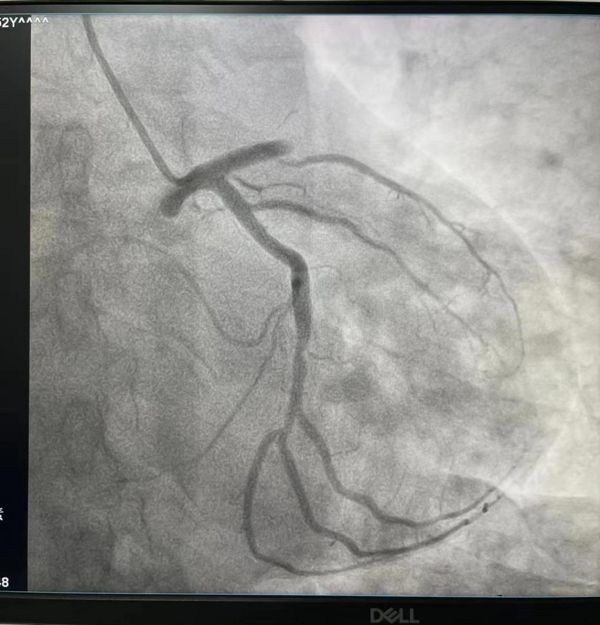

患者病情危重,入院后值班醫(yī)生趙娟副主任與護(hù)士李佳佳、王梅菊緊急將患者送往介入科,開(kāi)展急診手術(shù),術(shù)中患者持續(xù)性胸痛,血壓低,趙大夫,睢大夫和鄭大夫臨危不亂,給予對(duì)癥處理,造影結(jié)果顯示:患者前降支完全閉塞,遂進(jìn)行開(kāi)通,后置入一枚支架,手術(shù)幾經(jīng)波折,險(xiǎn)象環(huán)生,歷經(jīng)近一個(gè)小時(shí),終于完美收官,患者安返病房。此時(shí),患者家屬長(zhǎng)舒了一口氣,對(duì)各位醫(yī)護(hù)工作人員表達(dá)熱烈的感激之情,我科工作人員表示這是我們應(yīng)該做的,場(chǎng)面異常溫馨。